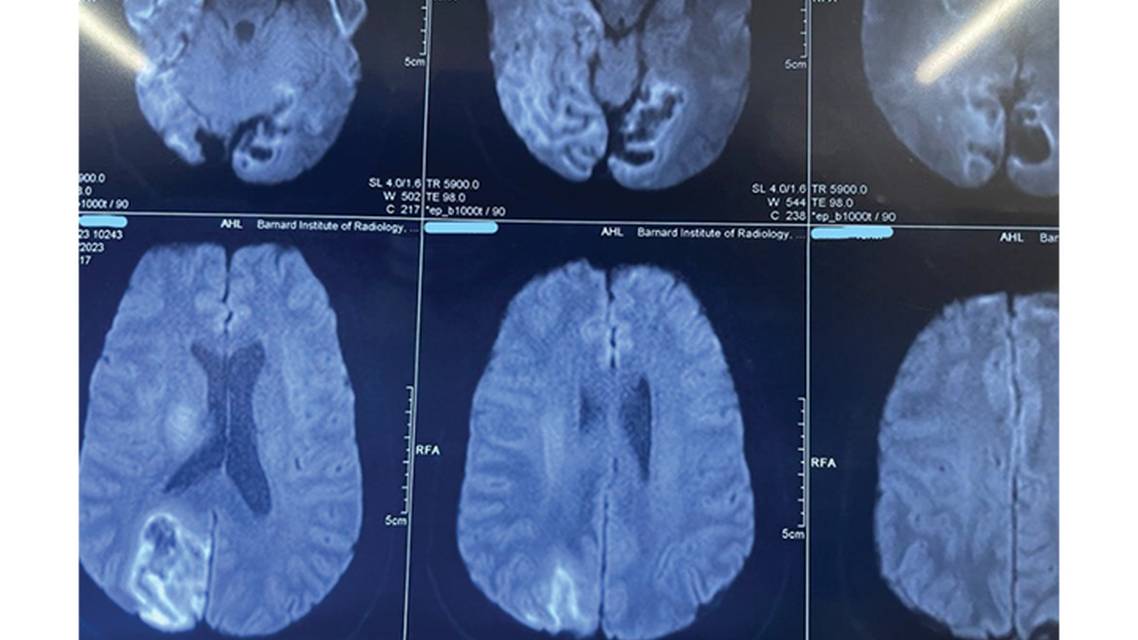

Detailed ophthalmologic evaluation revealed bilateral disc edema. Because the pupillary reaction was normal and no relative afferent pupillary defect was present, the optic disc edema was considered more likely to be attributable to papilledema than to papillitis. Brain MRI with contrast (Figure 1) showed diffusion restriction and contrast enhancement in the posterior cerebral artery territory, bilateral occipital cortices, and medial temporal lobe along with the right thalamus. There was residual edema of infarcted tissue causing narrowing of the cisternal spaces and compression of the lateral ventricles, suggesting intracranial pressure resulting in papilledema in the acute stage. Magnetic resonance angiogram (Figure 2) and venogram tested produced normal results. Subacute infarct with gyriform enhancement was noted (Figure 3) and cisternal cerebrospinal fluid spaces were reduced because of edema. Workup for connective tissue disorders (including antinuclear antibody and antineutrophil cytoplasmic antibody) was negative. EKG testing did not show any rhythm changes, and 2-dimensional echocardiography showed no structural abnormalities or clots. Workup for antiphospholipid antibodies was negative.